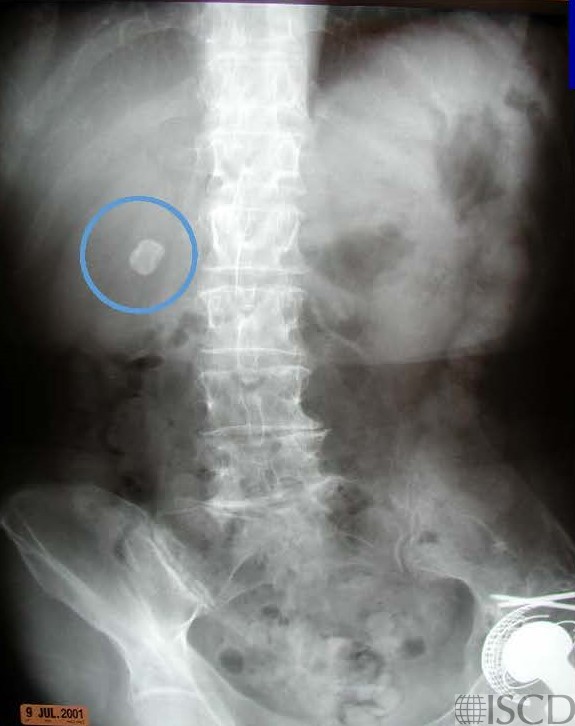

The accompanying radiograph shows the gallstone (blue circle).

There is a gallstone lateral to L1-L2 on the Hologic lumbar spine scan. The accompanying radiograph shows the gallstone (blue circle).